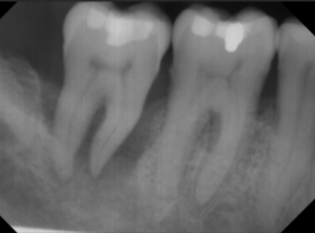

horizontal bone loss

parallel movement of alveolar crests towards the apex of the tooth

mild horizontal bone loss

blunting of alveolar crests and slight loss of height

loss of height around multiple teeth may involve furcation

moderate horizontal bone loss